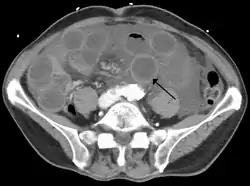

![]() تصوير مقطعي يبين حلقات متوسعة من الأمعاء الدقيقة مع جدران سميكة (السهم الأسود)، ونتائج مميِزة للأمعاء الإقفارية بسبب تخثر الوريد المساريقي العلوي. تصوير مقطعي يبين حلقات متوسعة من الأمعاء الدقيقة مع جدران سميكة (السهم الأسود)، ونتائج مميِزة للأمعاء الإقفارية بسبب تخثر الوريد المساريقي العلوي. | |